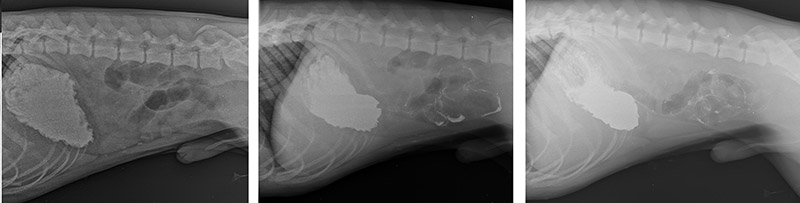

Чтобы исключить или подтвердить наличие инородного тела в ЖКТ необходимо сделать серею рентгенологических снимков с контрастным веществом (барий), которое предварительно выпаивается питомцу. Смысл исследования заключается в том, чтобы увидеть, как контрастное вещество распространяется по ЖКТ, для это в течение 12 часов через определенные промежутки времени делается рентгеновские снимки (в нашем центре для вашего удобства есть стационар, в котором вы можете оставить питомца на все время исследования)

При контрастном рентгенологическом исследовании, как видно на серии снимков контрастное вещество дальше желудка практически не проходит, не смотря на разницу между первым и последним снимком более 12 часов.